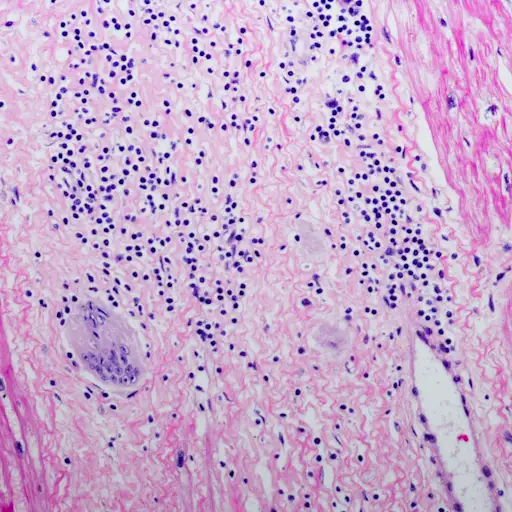

颗粒状酒渣鼻

肉芽肿性酒渣鼻与其余的酒渣鼻有些不同,仅占酒保病例的10%。Labadie博士解释说:“这不是四个主要子类型之一,但也许是一个小的子类型。”“It looks like rosacea, but it’s actually a predominance of a different type of cell in the skin,” So while this type looks super similar to the first two subtypes of rosacea, when you zoom in, you’ll see granulomas—or clusters of immune cells. Despite this difference,治疗Labadie博士说,Labadie博士说,与其他子类型大致相同。